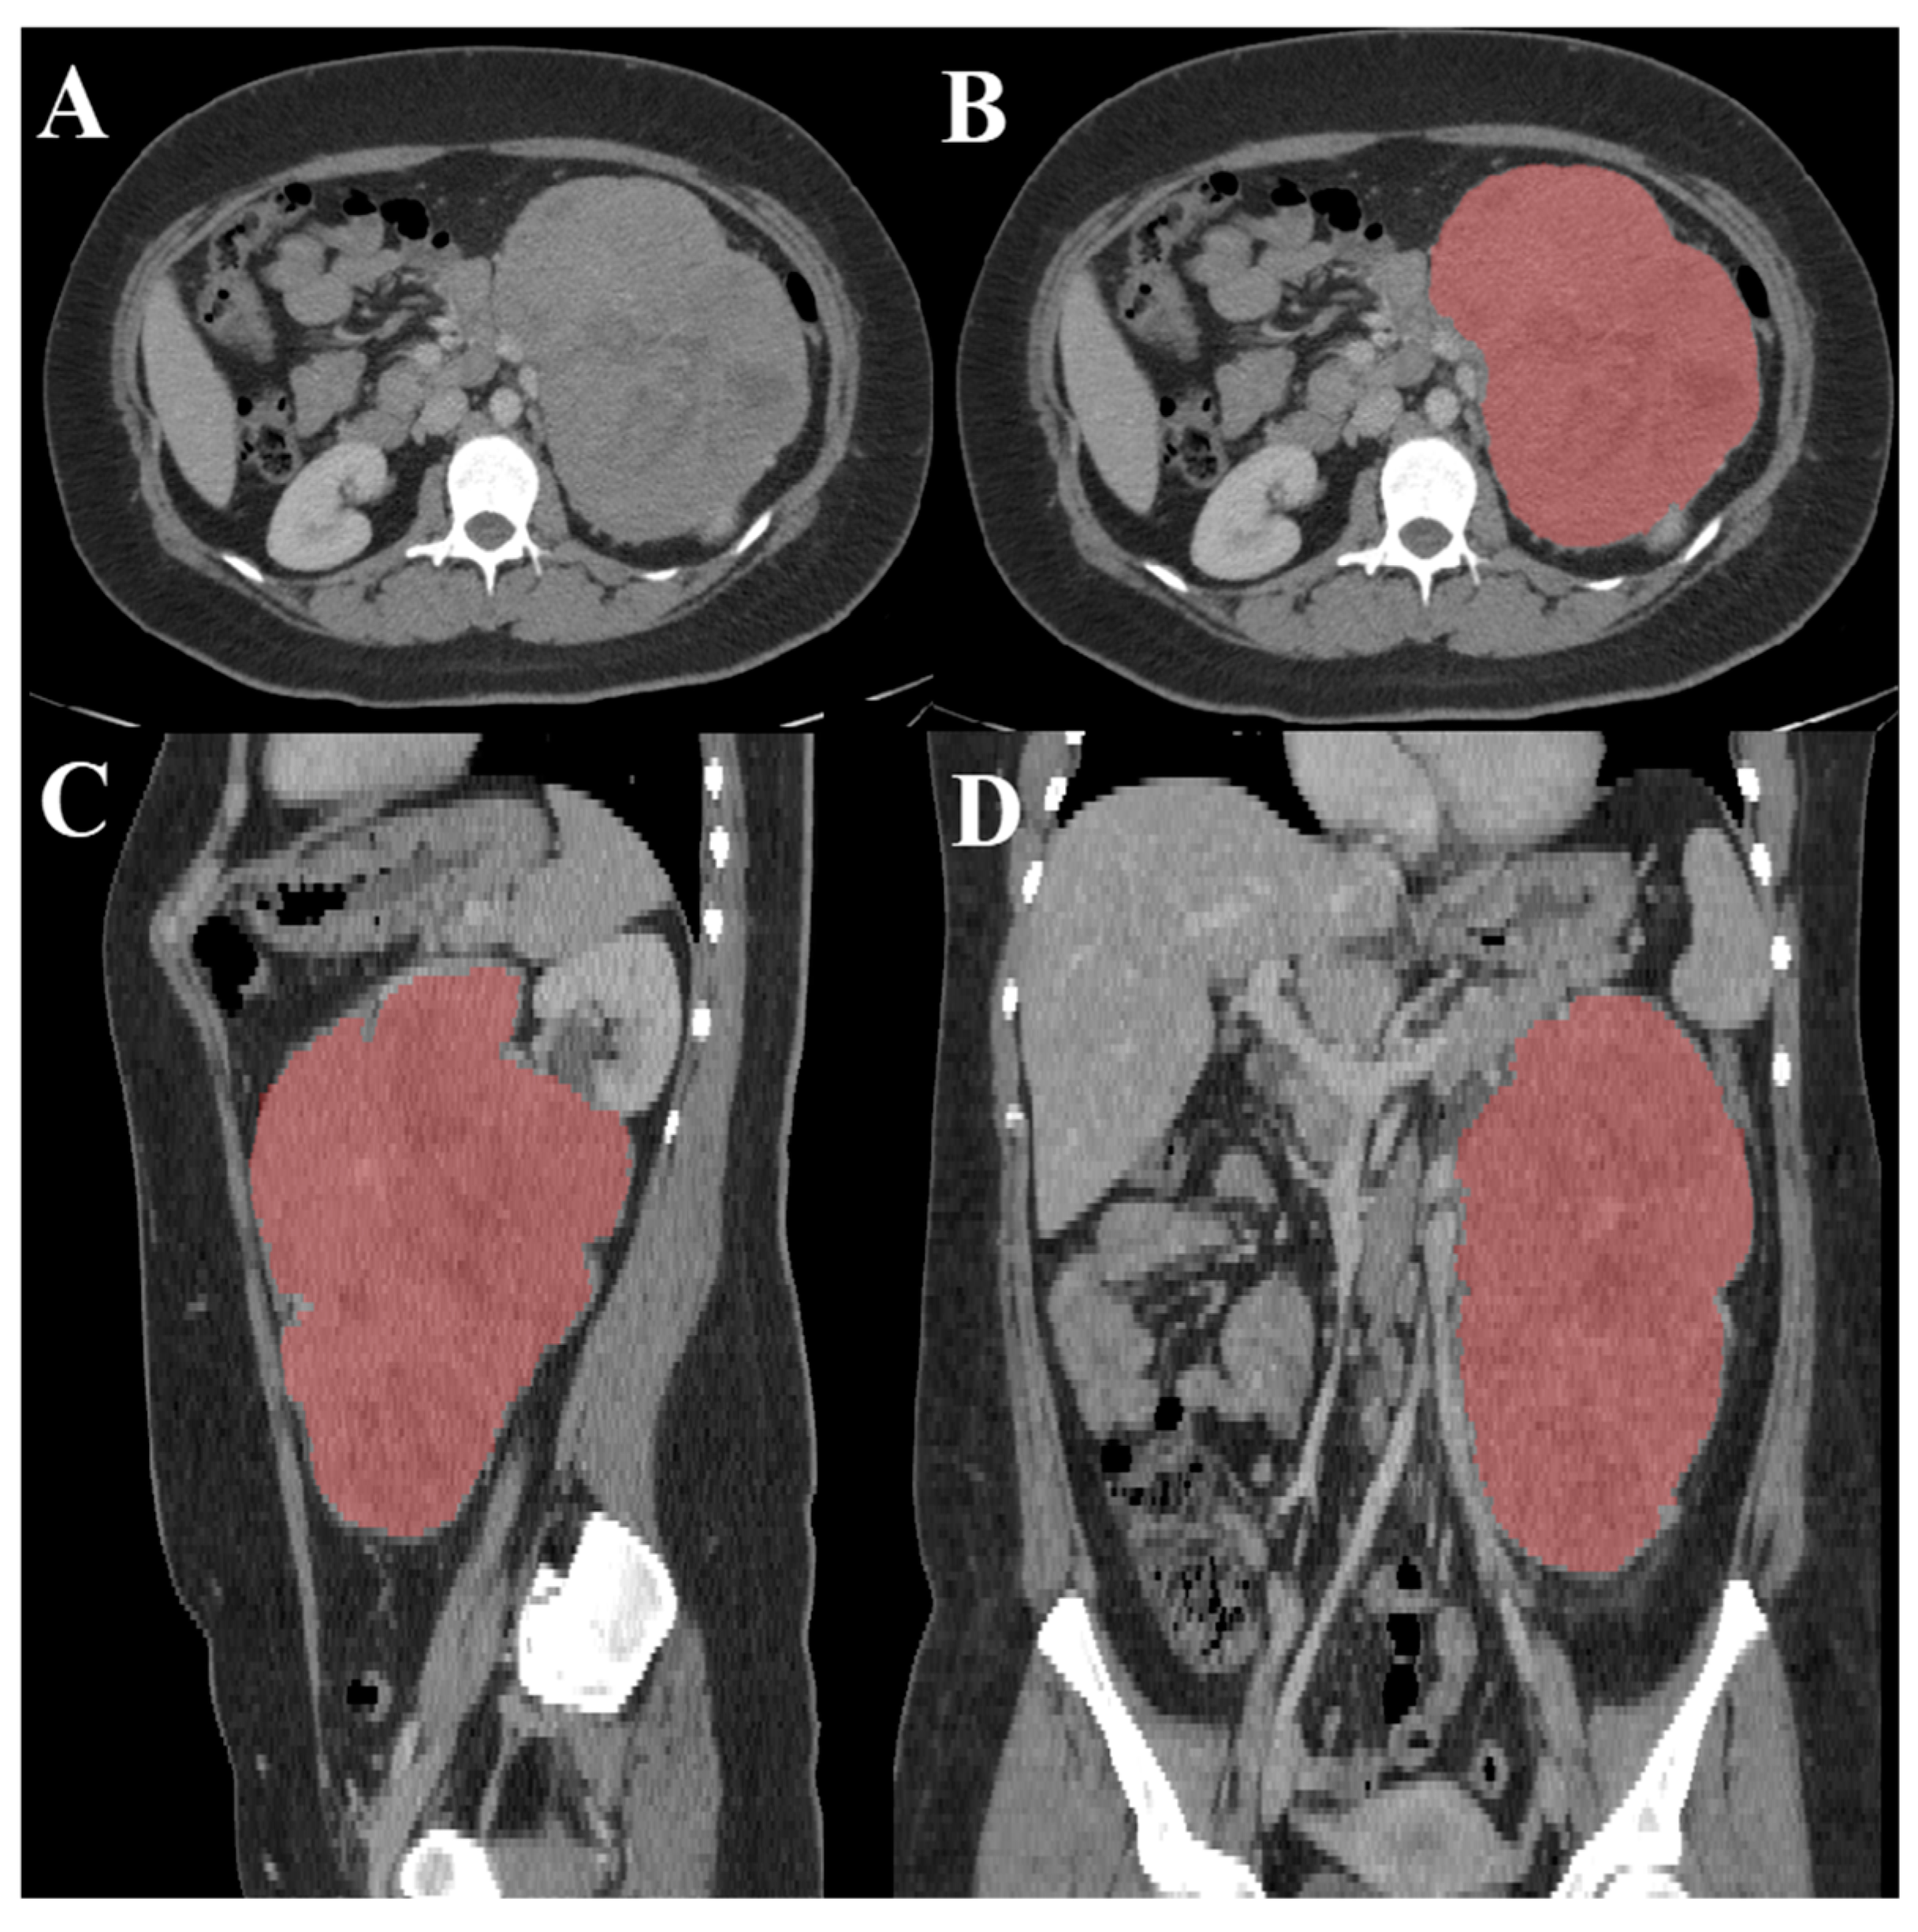

- Nolan, T., & Kirby, J. (2023, June 9). Voxel-level segmentation of pathologically-proven adrenocortical carcinoma with Ki-67 expression (adrenal-ACC-KI67-SEG). Voxel-level segmentation of pathologically-proven Adrenocortical carcinoma with Ki-67 expression (Adrenal-ACC-Ki67-Seg) - The Cancer Imaging Archive (TCIA) Public Access - Cancer Imaging Archive Wiki. https://wiki.cancerimagingarchive.net/pages/viewpage.action?pageId=93257945.

- Heller, N., Sathianathen, N., Kalapara, A., Walczak, E., Moore, K., Kaluzniak, H., ... & Weight, C. (2019). The kits19 challenge data: 300 kidney tumor cases with clinical context, ct semantic segmentations, and surgical outcomes. arXiv preprint arXiv:1904.00445.